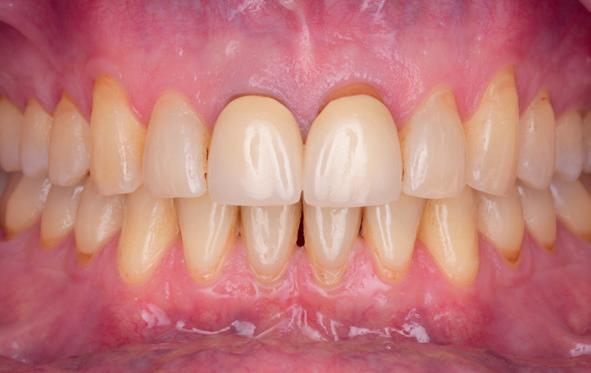

5. Beginsituatie voor behandeling

14. Direct postoperatief plaatsen

van de essix met 2 dummy tanden

15. Twee weken post operatief